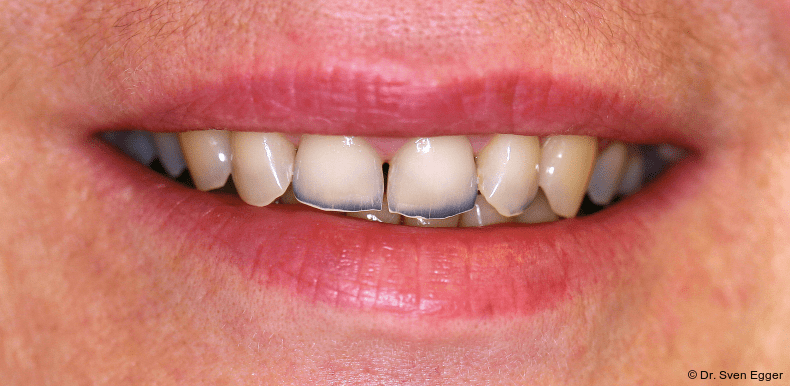

Bei der zahnmedizinischen Anamnese stellte sich ein hoher Konsum säurehaltiger Getränke (v. a. Coca-Cola light) heraus, welcher zu generalisierten Erosionen im Gebiss geführt hat. Die Zähne 36 und 47 wurden aufgrund endodontischer Vorbehandlung/Kronenfrakturen vor ca. vier Jahren entfernt. Der Leidensdruck, insbesondere verursacht durch die immer kürzer werdenden Frontzähne, bewog sie nach Aufklärung/Beratung zu einer Gesamtrestauration in allen vier Quadranten mit Presskeramikteilkronen und -veneers sowie drei Einzelzahnimplantaten.

Parodontal zeigen sich keine Auffälligkeiten. Der CMD-Kurzbefund zeigte eine Druckdolenz im Bereich M. masseter und M. temporalis. Die KG sind unauffällig.Die Zähne 17, 26 sind elongiert, 37 ist nach mesial gekippt. Es liegt ein Tiefbiss vor.

- Parafunktion mit massivem Zahnhartsubstanzverlust(Erosionen/Abrasionen) bei bestehender Deckbisssituation

- Störung der statischen und dynamischen Okklusion